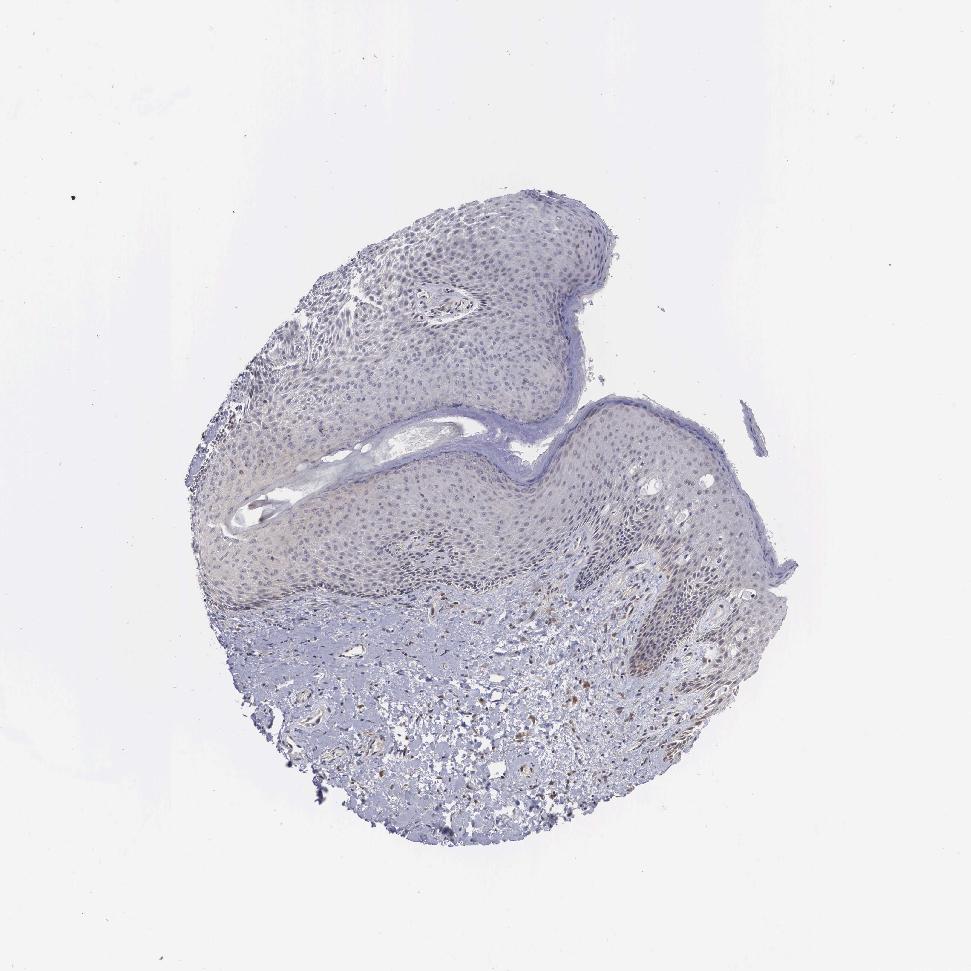

SKIN 2 - Antibody stainingi

Antibody staining in the annotated cell types in the current human tissue is reported as not detected, low, medium, or high, based on conventional immunohistochemistry profiling in selected tissues. This score is based on the combination of the staining intensity and fraction of stained cells.

Each image is clickable and will lead to virtual microscopy that enables deeper exploration of all samples and also displays staining intensity scores, fraction scores and subcellular localization as well as patient and tissue information for each sample.

Antibody HPA000603Antibody CAB025604

Epidermal cells Not detectedLow